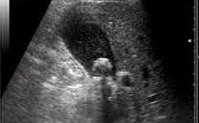

С помощью УЗИ желчного пузыря определяются анатомические параметры органа, выявляются холестаз и камни желчного пузыря; холестероз, фиброз, кальцинаты его стенок. В большинстве случаев калькулезный холецистит может быть диагностировано посредством эхографии. Пероральная или внутривенная холецистография дает представление о положении, величине, форме, контурах желчного пузыря, наличии деформаций и конкрементов. При признаках обтурации желчного протока может потребоваться выполнение чрескожной чреспеченочной холангиографии, РХПГ.